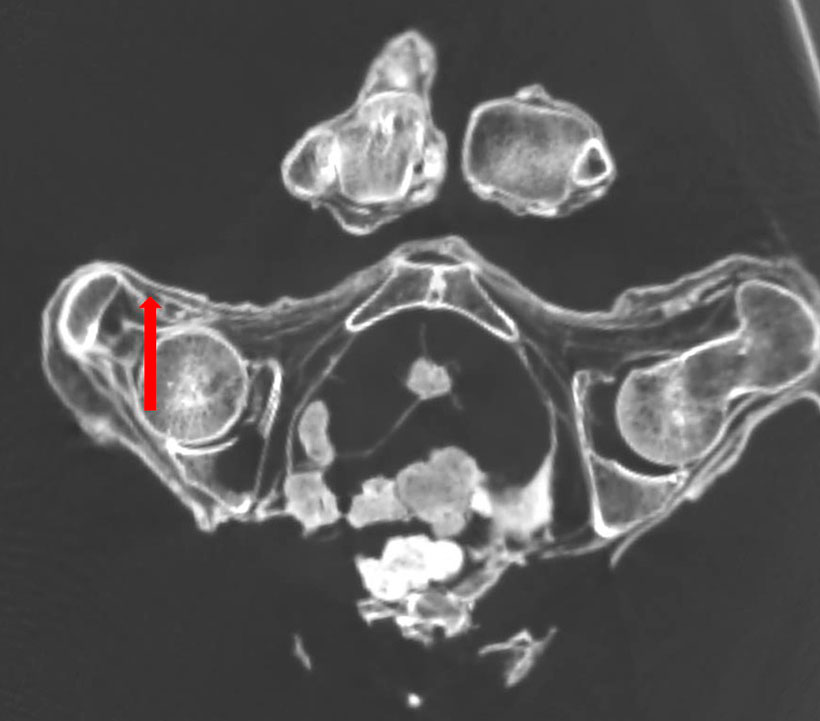

Деструкция костной ткани — горизонтальная плоскость:

Смещение тел II и III грудного позвонка, отёк межсуставного диска (указано стрелкой), полость в области тела VII грудного позвонка (обведено, сагиттальная плоскость). Имеется смещение тел II и III грудного позвонка, отёк межсуставного диска. В области тела VII грудного позвонка визуализируется полость, соответствующая гемангиоме.